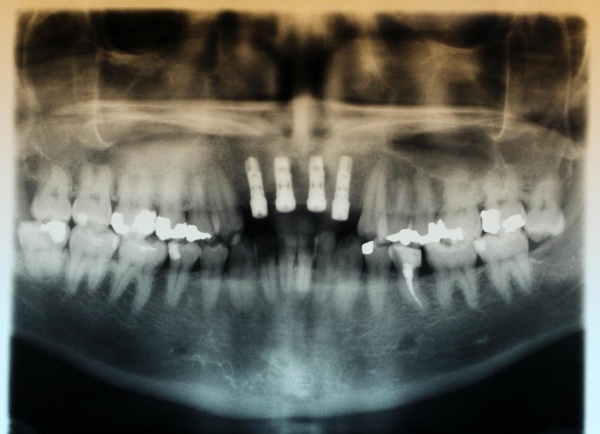

Nach achtwöchiger Ausheilzeit wurde im Mai 2012 eine 3D-Planung der Implantation bei unklarem Knochenangebot durchgeführt. Hierzu erfolgte bei Zahnlosigkeit zur Verankerung der Planungsschablonen im Juni 2012 die Insertion von drei Miniimplantaten im Oberkiefer und drei Miniimplantaten im Unterkiefer. Zur besseren Stabilisierung der schon vorhandenen Totalprothesen wurden Druckknöpfe in die Prothesen eingebracht. Nach Herstellung der Planungsschablonen wurde Ende Juni 2012 eine Denta-CT durchgeführt.

Im Oberkiefer konnten mit der Planungssoftware SkyPlanX der Firma Bredent 6 Implantate mit BoneSplit geplant werden (Abb. 2), im Unterkiefer war eine Implantation aufgrund ungenügenden Knochenangebots nicht möglich.

Im August 2012 erfolgten die 3D-gestützte Implantation (6 Implantate, Firma Nobel Biocare, System Active) im Oberkiefer mit Bone Split sowie eine An- und Auflagerungsosteoplastik vom linken Beckenkamm im Unterkiefer nach Entfernung der Miniimplantate (Abb. 3). Nach komplikationsloser Einheilung wurde im Dezember 2012 die Materialentfernung und Implantation im Unterkiefer (6 Implantate, Firma Nobel Biocare, System Active) durchgeführt (Abb. 4). Die Osseointegration verlief ungestört. Aufgrund der ungenügenden Weichgewebssituation im Unterkiefer erfolgte an jedem Implantat bei Freilegung eine Vestibulumplastik mit Einlagerung einer bioresorbierbaren Membran (Firma Botiss, Mucoderm, Abb. 5 und 6). Die endgültige prothetische Versorgung erfolgte durch den truppenzahnärztlichen Kollegen in der Stammeinheit des Patienten (Zahnarztgruppe Nordholz / SanZ Celle) mit einer gaumenfreien implantatgetragenen Teleskopprothese im Ober- und Unterkiefer, die eine festsitzend-herausnehmbare vollständige stomatognathe Rehabilitation des Patienten ermöglichte (Abb. 7 und 8). Er wurde zum halbjährlichen Recall angehalten.